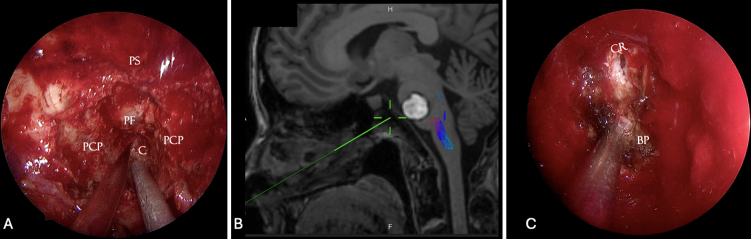

Observations: The authors report the case of a 54-year-old woman with a ventral pontine cavernous malformation (CM) presenting with recurrent hemorrhagic episodes, all resolving without neurological sequelae. Based on the anterior midline location of the lesion within the pons and the posterolateral displacement of the corticospinal tracts (CSTs) on preoperative tractography, an EETA was deemed the most suitable approach. Gross-total removal was achieved without neurological worsening or postoperative CSF leakage.

Lessons: This case supports the use of EETA as a safe and effective surgical route for ventral pontine CMs with anterior surface presentation. Accurate preoperative planning, including assessment of CST displacement via diffusion tensor imaging, and direct intraoperative cortical stimualtion are essential for identifying a safe entry point. Although technically demanding and not universally applicable, EETA offers a direct surgical corridor that minimizes neurovascular manipulation and facilitates favorable outcomes in selected cases. https://thejns.org/doi/10.3171/CASE25356.